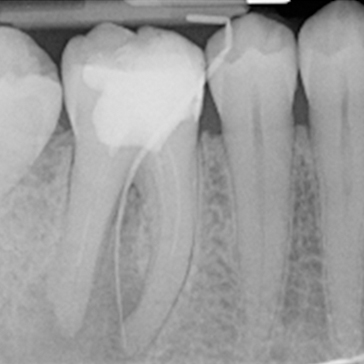

Case 3. Re-RCT of UR6